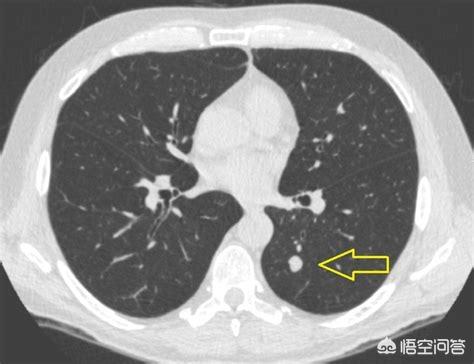

Il y a deux jours, j'ai lu un cas, le patient, un homme de 57 ans, a été examiné pendant trois ans et a enregistré le processus de transformation d'un nodule de 0,5 cm en cancer du poumon ; à chaque examen, le nodule augmente de taille, mais le patient n'a pas opté pour la chirurgie.

La flèche pointe vers le nodule, qui était très petit lorsqu'il a été découvert en mars 2016, environ 0,5 cm, et maintenant les examens médicaux de routine révèlent de très nombreux nodules comme celui-ci.Il n'existe aucun moyen de déterminer s'il s'agit d'une tumeur bénigne ou maligne sur les images, seule l'option de l'examen, et l'examen et le suivi constituent également le meilleur outil.

Sept mois plus tard, lors du deuxième examen de suivi en octobre 2016, il était évident que ce nodule était devenu plus grand et plus rond. Le nodule élargi lors du suivi devait alerter sur la possibilité d'une tumeur maligne, mais cette patiente n'a toujours pas opté pour la chirurgie.

Après encore 1 an et 2 mois, le troisième examen en décembre 2017.Vous pouvez voir que ce nodule est beaucoup plus grand qu'avant, les signes malins sont lobulés et il est devenu solide à l'intérieur, ces signes diagnostiquent le cancer du poumon fondamentalement, mais le patient n'a toujours pas été opéré.

Le nodule s'était transformé en masse (>3cm) et ce cancer du poumon pouvait être un cas d'école, avec fondamentalement tous les signes de malignité qui soutiennent le cancer du poumon.Bords irréguliers, lobulation, bavures et signes d'arrachement pleural.

Heureusement, aucune lésion métastatique n'a encore été observée et l'ablation chirurgicale est encore possible. Si le traitement n'est pas encore une option, revenez pour un examen dans un an et vous pouvez vous attendre à de multiples changements métastatiques. En fait, lors du deuxième examen, les lésions étaient plus importantes et une résection chirurgicale aurait dû être effectuée à ce moment-là, sans récidive ni métastase. À mesure que la lésion grossit, il peut y avoir des cellules cancéreuses dans le sang, et le risque de récidive et de métastase est alors plus élevé.